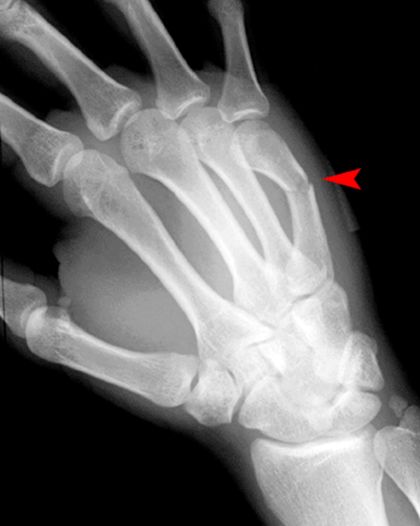

Bennett Fracture

第一掌骨基底部

关节内骨折伴脱位–背侧半脱位

轴向压力